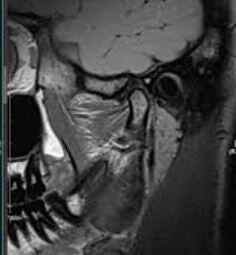

MRI TMJ Images

Our TMJ MRI evaluation service provides comprehensive radiologic interpretation of the soft tissue structures of the temporomandibular joints, including articular disc position, morphology, joint effusion, retro-discal tissue, and inflammatory changes.

Reports include evaluation in both open and closed mouth positions (if available) and are ideal for diagnosing internal derangement, disc displacement (with or without reduction), joint effusion, and signs of inflammatory arthropathy.